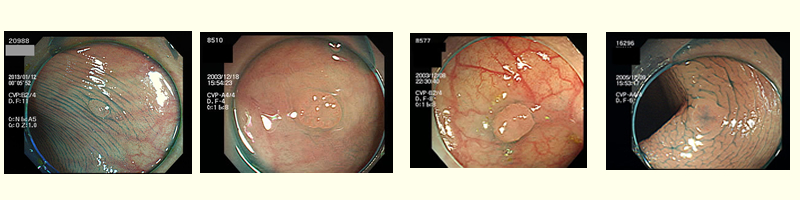

上の4枚は2〜4ミリの腺腫です。4枚とも「まだ良性」ですが、高度異型腺腫(グループ4)と言いまして「1年後には癌になっていたであろう」と予測される病変です。

このような「微小・高危険・腺腫」は精度の高い内視鏡では日常的に発見されます。しかし、では、全てが発見されているか?と言うと・・・・・・残念ながら、このような病変は経験豊富な専門医でも見落とされる危険があります。

つまり厳密には「癌を見落とす」のは稀で、多くの場合は「微小な腺腫を見落とし、癌化の予防に失敗した」ということなのです。

患者さんは、このような微小腺腫も確実に見つけてもらいたいと期待して検査に臨む訳で、それが「理想的な検査」なのですが・・・現実には100%は無理です。